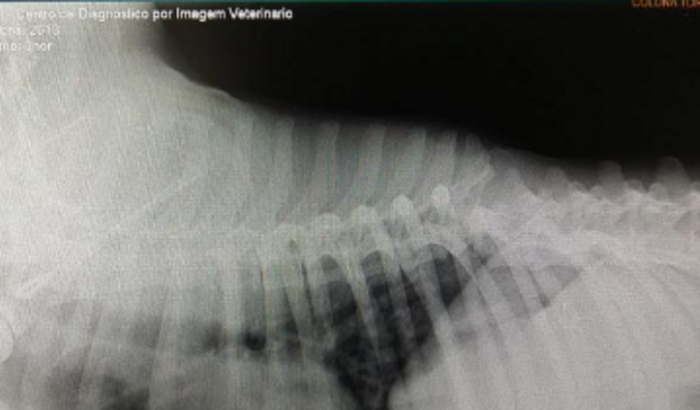

Eu sou Luiz Douglas e criei essa vaquinha para poder arrecadar 6.000 mil reais, para realizar a cirurgia na coluna do meu pet THOR. Thor a 8 dias atrás foi atropelado por uma moto e teve fratura na vértebra T10, e na t11, com grandes possiblidades de haver uma ruptura medular. Ele ficou paraplégico, e tenho condições para cadeira de rodas, mas a cadeira não vai adiantar antes de ser realizado uma cirurgia. Obrigado pela atenção, lembra que qualquer valor que puder enviar já ajuda meu amigo